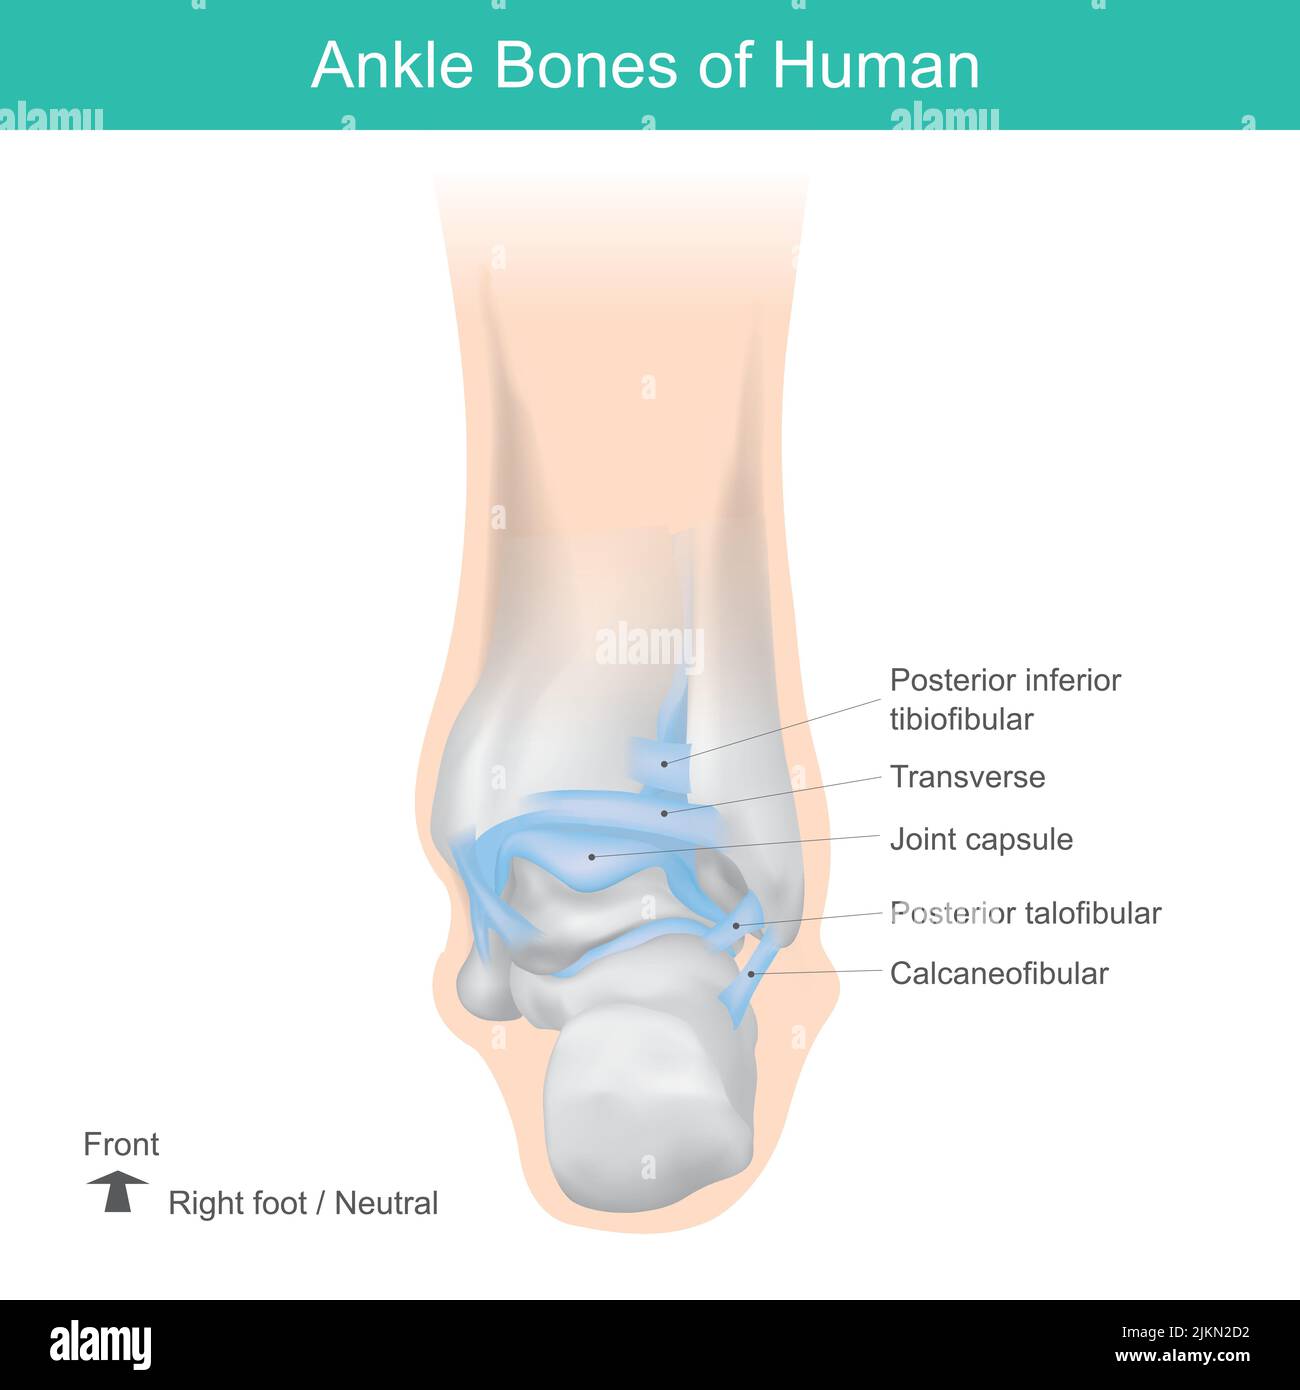

RF2JKN2D2–OS de la cheville humaine, position correcte os de la cheville humaine. Illustration Anatomy Health Care.

RF2JNRK18–Os de cheville de l'homme. Positionnement correct des os de la cheville chez l'homme. Illustration soins de santé.

RF2X200ED–L'anatomie de l'articulation de la cheville. Région talocrurale ou os sauteur. Partie du corps humain où le pied et la jambe se rencontrent. Fascia plantaire et tendon d'Achille